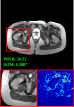

Clinical datasets. Clinical datasets include Brain (with T1 reference contrast and T2-FLAIR target contrast) and Pelvic (with T1 reference contrast and T2 target contrast). Specifically, the brain dataset consists of 637 slices from healthy subjects and 305 slices from tumor subjects. Among them, 512 slices of healthy subjects are utilized for training, 125 slices of healthy subjects are employed for validation and testing, and 305 slices of tumor subjects are used for additional testing. The pelvic dataset comprises 1600 slices, with a training, validation, and test split ratio of 7:1:2. The raw clinical datasets are generated by scanning with a 3T Philips Ingenia MRI Scanner. The scanning parameters for the brain are TE (T1): 2.3ms, TE (T2-FLAIR): 120ms. The scanning parameters for the pelvic are TE (T1): shortest, TE (T2): 130ms. The sum-of-squares (SOS) method is used for coil combination.

Figure 5 provides the qualitative comparison of the various methods on the four datasets at a scale of 4. The top, second, third, and bottom rows are the SR results under the FastMRI, clinical brain, clinical tumor and clinical pelvic datasets, respectively. The red boxes indicate the zoom-in region of complicated anatomical structures along with their corresponding error maps. Note that the brighter textures in the error maps, the lower the quality of the reconstructed images. As can be seen, compared to methods based on Transformers and CNNs, diffusion-based methods like DisC-Diff and DiffMSR (Ours) are capable of reconstructing high-realistic images with promising reconstruction metric scores (PSNR and SSIM). Nevertheless, while DisC-Diff can reconstruct high-precision MR images, it does not preserve the structure present in the original HR images, introducing some additional information that can affect medical diagnosis. In contrast, our method combines DM and PLWformer, which can preserve the original image’s structure while restoring high-frequency information.